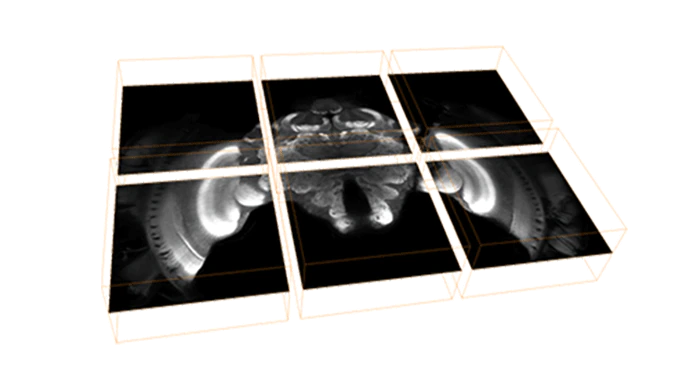

XLVolume – Large Data Management

Manage and visualize very large amounts of volume data of up to several terabytes. Go far beyond the limit of the available system memory.

The multiresolution technique used in XLVolume extension enables interactive visualization and navigation through large data sets. Learn more